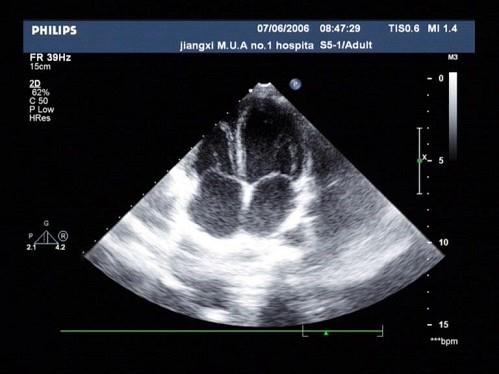

如图切面称为哪种超声心动图切面?(?)A.心尖四腔B.心尖短轴C.左室长轴D.心尖二腔E.大动脉短轴

问题 如图切面称为哪种超声心动图切面?(?)

选项 A.心尖四腔 B.心尖短轴 C.左室长轴 D.心尖二腔 E.大动脉短轴

答案 A